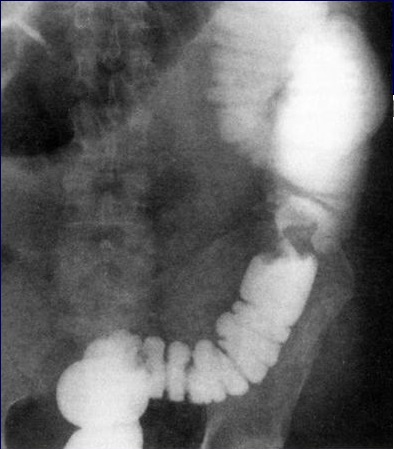

Image de

soustraction laculaire et stenosant d'une

adenocarcinoma du colon descendant sigmoidienne .

Lavemant baryte mono de contrast |

Image radiologique de lavement

baryte en mono de contrast avec aspect de soustraction

stenosant irreguliere d'une adenocarcinome du colon

sigmoide . La bord de la portion stenosant est tres

irregulie et durcissement . |